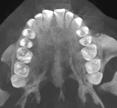

En la radiografía lateral de cráneo ( Figura 6 ) se ve la línea estética de Rickets, que el labio superior se encuentra a +0.5 mm y el inferior a -2 mm. En las mediciones cefalométricas más importantes en la figura 11 un ANB de 5º, GoGn-SN de 33º y FMA de 21º crecimiento normodivergente y Witts de -1 mm. A los criterios dentales encontramos

1-PLT de 129º e IMPA 99º proinclinación de incisivos tanto superiores como inferiores. En la radiografía panorámica (Figura 7), la presencia de 32 órganos dentarios, con terceros molares inferiores aún sin erupcionar y terceros molares superiores

7. Radiografía panorámica.

Figura 8. Cortes sagital, inclinaciones dentales superior e inferior, axial tomográfico de las arcadas.

Figura

de clase II esquelética y dental

ya erupcionados, falta de paralelismo radicular, asimetría condilar, articulación temporomandibular (ATM) izquierda afectada.

Estudios tomográficos

En el corte sagital ( Figura 8 ) se muestran las inclinaciones dentales alteradas hacia vestibular de ambos incisivos. Finalmente en una vista

axial la forma de arcos cuadrada y la malposición dental clasificada como apiñamiento leve.

Panorámicas de inicio a fin (Figura 16) el paralelismo radicular, genera estabilidad a largo plazo en el tratamiento. Se extrajeron los terceros molares para eliminar discrepancia posterior y lograr adecuada

Figura 16. Radiografías panorámicas. a) Inicio. b) Progreso. c) Final.